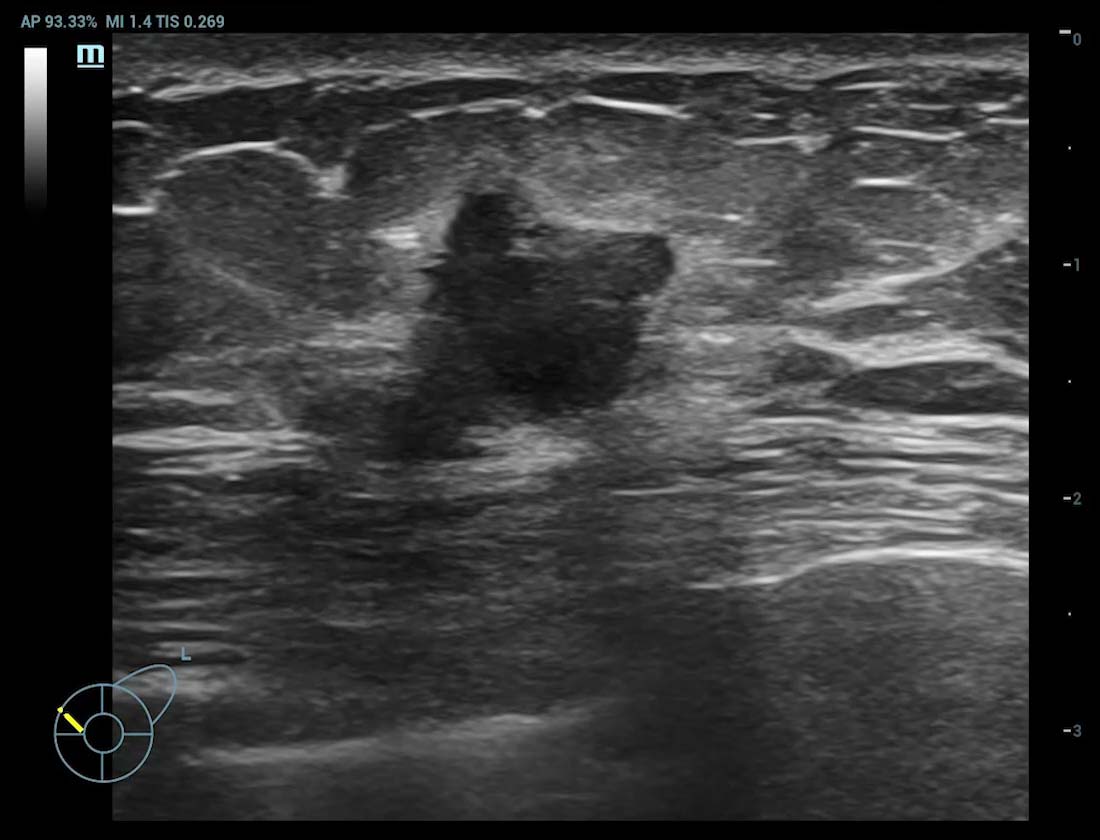

Ultra Micro Angiography (UMA)

UMA migliora la sicurezza diagnostica ampliando la visibilitĂ dei flussi sanguigni fino al livello dei vasi piĂč piccoli, con una sensibilitĂ e una risoluzione superiori.

Tumore alla tiroide sUMA